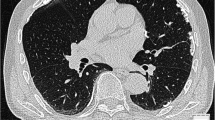

Typical consequences of years of asbestos exposure are, in addition to the malignant diseases bronchial carcinoma or pleural mesothelioma, in particular the development of pulmonary fibrosis, pleurisy or the manifestation of pleural plaques [2]. These changes result in restrictive lung dysfunction with a reduction of all volumes with normal to little change in the FEV1/FVC ratio. There is also a reduction in the diffusion capacity for CO (DLCO) [3]. In diagnostic imaging, low-dose high-resolution computed tomography of the chest (HR-TCT) is more suitable than chest X-ray examinations for assessing typical pathological processes of the lung parenchyma and pleura [4, 5]. Since 2017, low-dose HR-TCT has been established in Germany as an important diagnostic tool for the early detection of asbestos-related diseases in formerly asbestos-exposed individuals [6].

Computed tomography examination

The acquisition of HR-TCT examinations was carried out in compliance with a defined technical standard with uniform acquisition and reconstruction parameters. During the evaluation of the CT data sets, the slice thickness, the number of slices, the type of reconstruction, the dose, and the positioning of the patient were documented in accordance with the recommendations of the Working Group for Diagnostic Radiology in Occupational and Environmental Diseases (AG DRauE) of the German Roentgen Society [27]. Based on these technical criteria, each dataset was rated with a quality criterion from 1 to 4 [28].

The CT datasets were semi-quantitatively assessed using the International Classification of Occupational and Environmental Respiratory Diseases (ICOERD) according to Hering et al. [8]. ICOERD is considered the current standard for CT assessment of pneumoconiosis [29]. It is used to evaluate both the lungs and pleura. Lung changes are assessed by round opacities, irregular and/or linear opacities (divided into intra- and interlobular), ground glass, honeycombing, consolidations, and emphysema formations.

The ICOERD can be used to assign a score for each of the categories mentioned above: in the data sheet, the lung is divided into an upper (U), middle (M) and lower (L) field per side. Up to three points can be awarded per field and side depending on the disease-related parenchymal changes. Thus, values from 0–18 points are possible in the evaluation of lung changes for each category. For a reliable diagnosis of asbestosis, bilateral irregular and/or linear opacities with a score ≥ 2 or bilateral honeycombing with a score ≥ 2 are required findings in HR-TCT (according to Helsinki Criteria) [30].

With regard to the pleura, visceral findings are distinguished from parietal findings. The parietal type can show flat, spindle- or tableland-shaped thickenings and is typical of asbestos-related changes. Visceral findings occur as circumscribed thickening of the pleura and may also have other causes but do not rule out an asbestos-related genesis [7, 8]. Pleural findings are classified in the ICOERD according to the location of the pleural plaques in the right and left side as well as in the upper (U), middle (M), and lower (L) field, resulting in a possible pleural score of 0–6 points.

Of the 72 HR-TCT data sets, 59 could be assigned to quality 1 (no assessment limitation), 8 to quality 2 (slightly limited assessment), 3 to quality 3 (significantly limited assessment), and 0 to quality 4 (no assessment possible). Quality information was not available for two patients.

Evaluation of the CT data sets according to ICOERD reveals the following results: 57 of the 72 patients show radiologic findings indicative of pulmonary fibrosis (i.e., ≥ 2 points in fibrosis score = Score A). The extent of radiologically detectable irregular/linear opacities is rather low (median 3 points, range 0–10 points), and the maximum score in the patient collective is 10 points (n = 1). Approximately 65% of all patients have score values between 2 and 4 points (out of a maximum possible 18 points). Honeycombing as the final form of pulmonary fibrosis is seen in only two cases, each scored as 1 point.

Pleural plaques (Score B) were found in 58 patients (median 4 points, range 0–6 points); the most frequently assigned and highest score is 6 points (n = 17), followed by 5 and 4 points (each n = 10). Fourteen of these 17 patients with a score of 6 (82.4%) have concomitant cardiac diseases. Subjects with obstructive ventilatory disorder (sub-2) or a lung function pattern indicating emphysema (sub-3) show a homogeneous distribution of score values (both median 3 points, range 0–6 points). In patients without other pulmonary or cardiac diseases, four subjects without detectable pleural plaques were identified (median 2 points, range 0–6 points).

Of the whole study collective, nine subjects show signs of fibrosis but do not have pleural plaques. Ten patients have pleural plaques without fibrosis. Both signs of fibrosis and pleural plaques were found in 53 patients.

The frequency distribution of the newly observed additional parameters is shown in Table 3. Subpleural curvilinear lines (n = 39) and parenchymal bands (n = 29) show the highest prevalence with the widest range in the results, whereas the occurrence of RA (n = 9), and EF (n = 5) is rarely noted. The maximum values of SC and PB are 5 points each. Of 72 patients, 22 have no findings of an additional parameter.